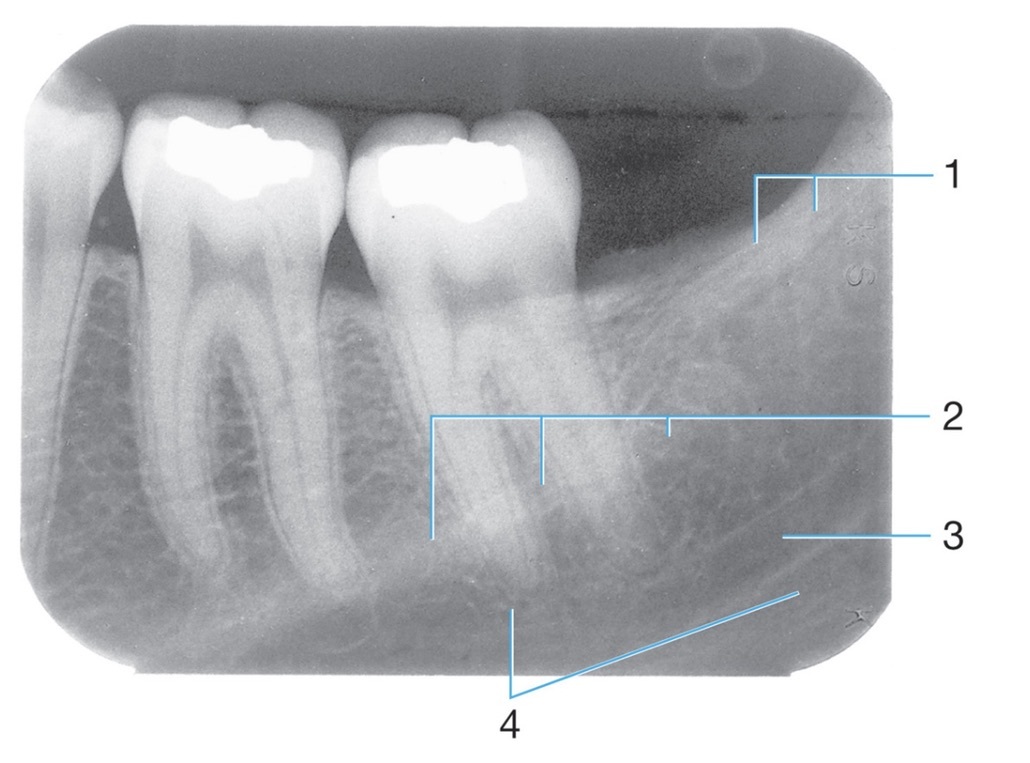

1.

Amalgam

2.

Radiopaque amalgam restorations

Mylohyoid ridge

Identify #1.

Border of maxillary sinus

Identify #3.

Nutrient foramen